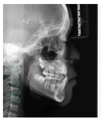

头颅侧位片示:下颌相对颅底位置靠前,趋向Ⅲ类错

,上下切牙舌腭向倾斜,骨龄CS1起始期。

治疗结果:总疗程共19个月,矫治后患者上颌双侧中切牙基本牵引至正常位置,左上恒中切牙及左下恒中切牙反

解除,上前牙恢复正常突度及倾斜度,下前牙恢复正常突度,稍舌倾。上下颌切牙覆

覆盖正常。上颌双侧恒尖牙未萌,间隙保留,左上恒尖牙异位好转,牙冠近中向倾斜程度减轻。下颌缺失右侧恒侧切牙,间隙关闭并排列整齐。通过慢速扩弓与及时拔除萌出通道上相应乳牙及多生牙,上下颌前磨牙、磨牙自然萌出到正常位置并建

患者治疗前后头影测量分析结果

| 北京大学分析法 | ||||

|---|---|---|---|---|

| 测量结果 | 治疗前 | 治疗后 | 标准值 | 诊断提示 |

| 骨测量 | ||||

| SNA | 84.5° | 84.7° | 82.3±3.5 | 上颌相对颅底位置正常 |

| SNB | 81.9° | 82.9° | 77.6±2.9 | 下颌相对颅底位置靠前 |

| ANB | 2.6° | 1.8° | 4.7±1.4 | 趋向Ⅲ类错![]() |

| FH-NPo | 87.4° | 89° | 83.1±3 | 颏部前突 |

| NA-Apo | 2.9° | 1.3° | 10.3±3.2 | 上颌相对面部后缩 |

| FMA | 28.1° | 28.1° | 31.8±4.4 | 均角型 |

| SGn-FH | 62.1° | 61.3° | 65.5±2.9 | 聚合生长型,颏部前突 |

| MP-SN- | 32.5° | 33° | 35.8±3.6 | 下颌提陡度、面部高度适宜 |

| Po-NB | 2mm | 2mm | 0.2±1.3 | 颏部发育量较大,颏部前突 |

| 牙测量 | ||||

| U1-NA | -1.2mm | 3.5mm | 3.1±1.6 | 上中切牙突度正常 |

| U1-NA | 7° | 18.2° | 22.4±5.2 | 上中切牙倾斜度正常 |

| L1-NB | 3.5mm | 3.5mm | 6±1.5 | 下中切牙后缩 |

| L1-NB | 19.4° | 16° | 32.7±5 | 下中切牙舌向倾斜 |

| U1-L1 | 151.1° | 144.1° | 122±6 | 上下前部牙弓突度较小 |

| U1-SN | 91.5° | 102.9° | 104.8±5.3 | 下中切牙相对前颅底平面倾斜度正常 |

| IMPA | 85.1° | 80.1° | 94.7±5.2 | 下中切牙相对下颌平面舌向倾斜 |